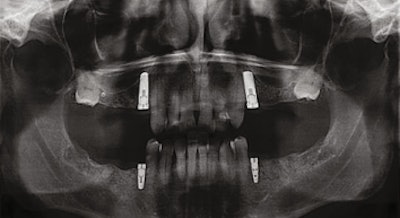

Panoramic radiograph (circa 2016) taken before extractions.

Panoramic radiograph (circa 2016) following extraction of all posterior teeth except the mandibular first bicuspids. Impacted third molars were not removed due to the distinct possibility of ankylosis and the potential for fracturing the posterior wall and floor of the maxillary antrum.

Panoramic radiograph (March 2017) after placement of dental implants and treatment planned for a shortened dental arch.